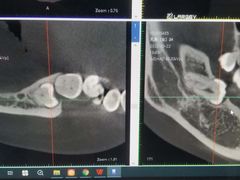

• Dr.Z dental仁康种植矫正中心

• -Dr.Z dental仁康种植矫正中心

icecreamangle | 22-08-20

报错